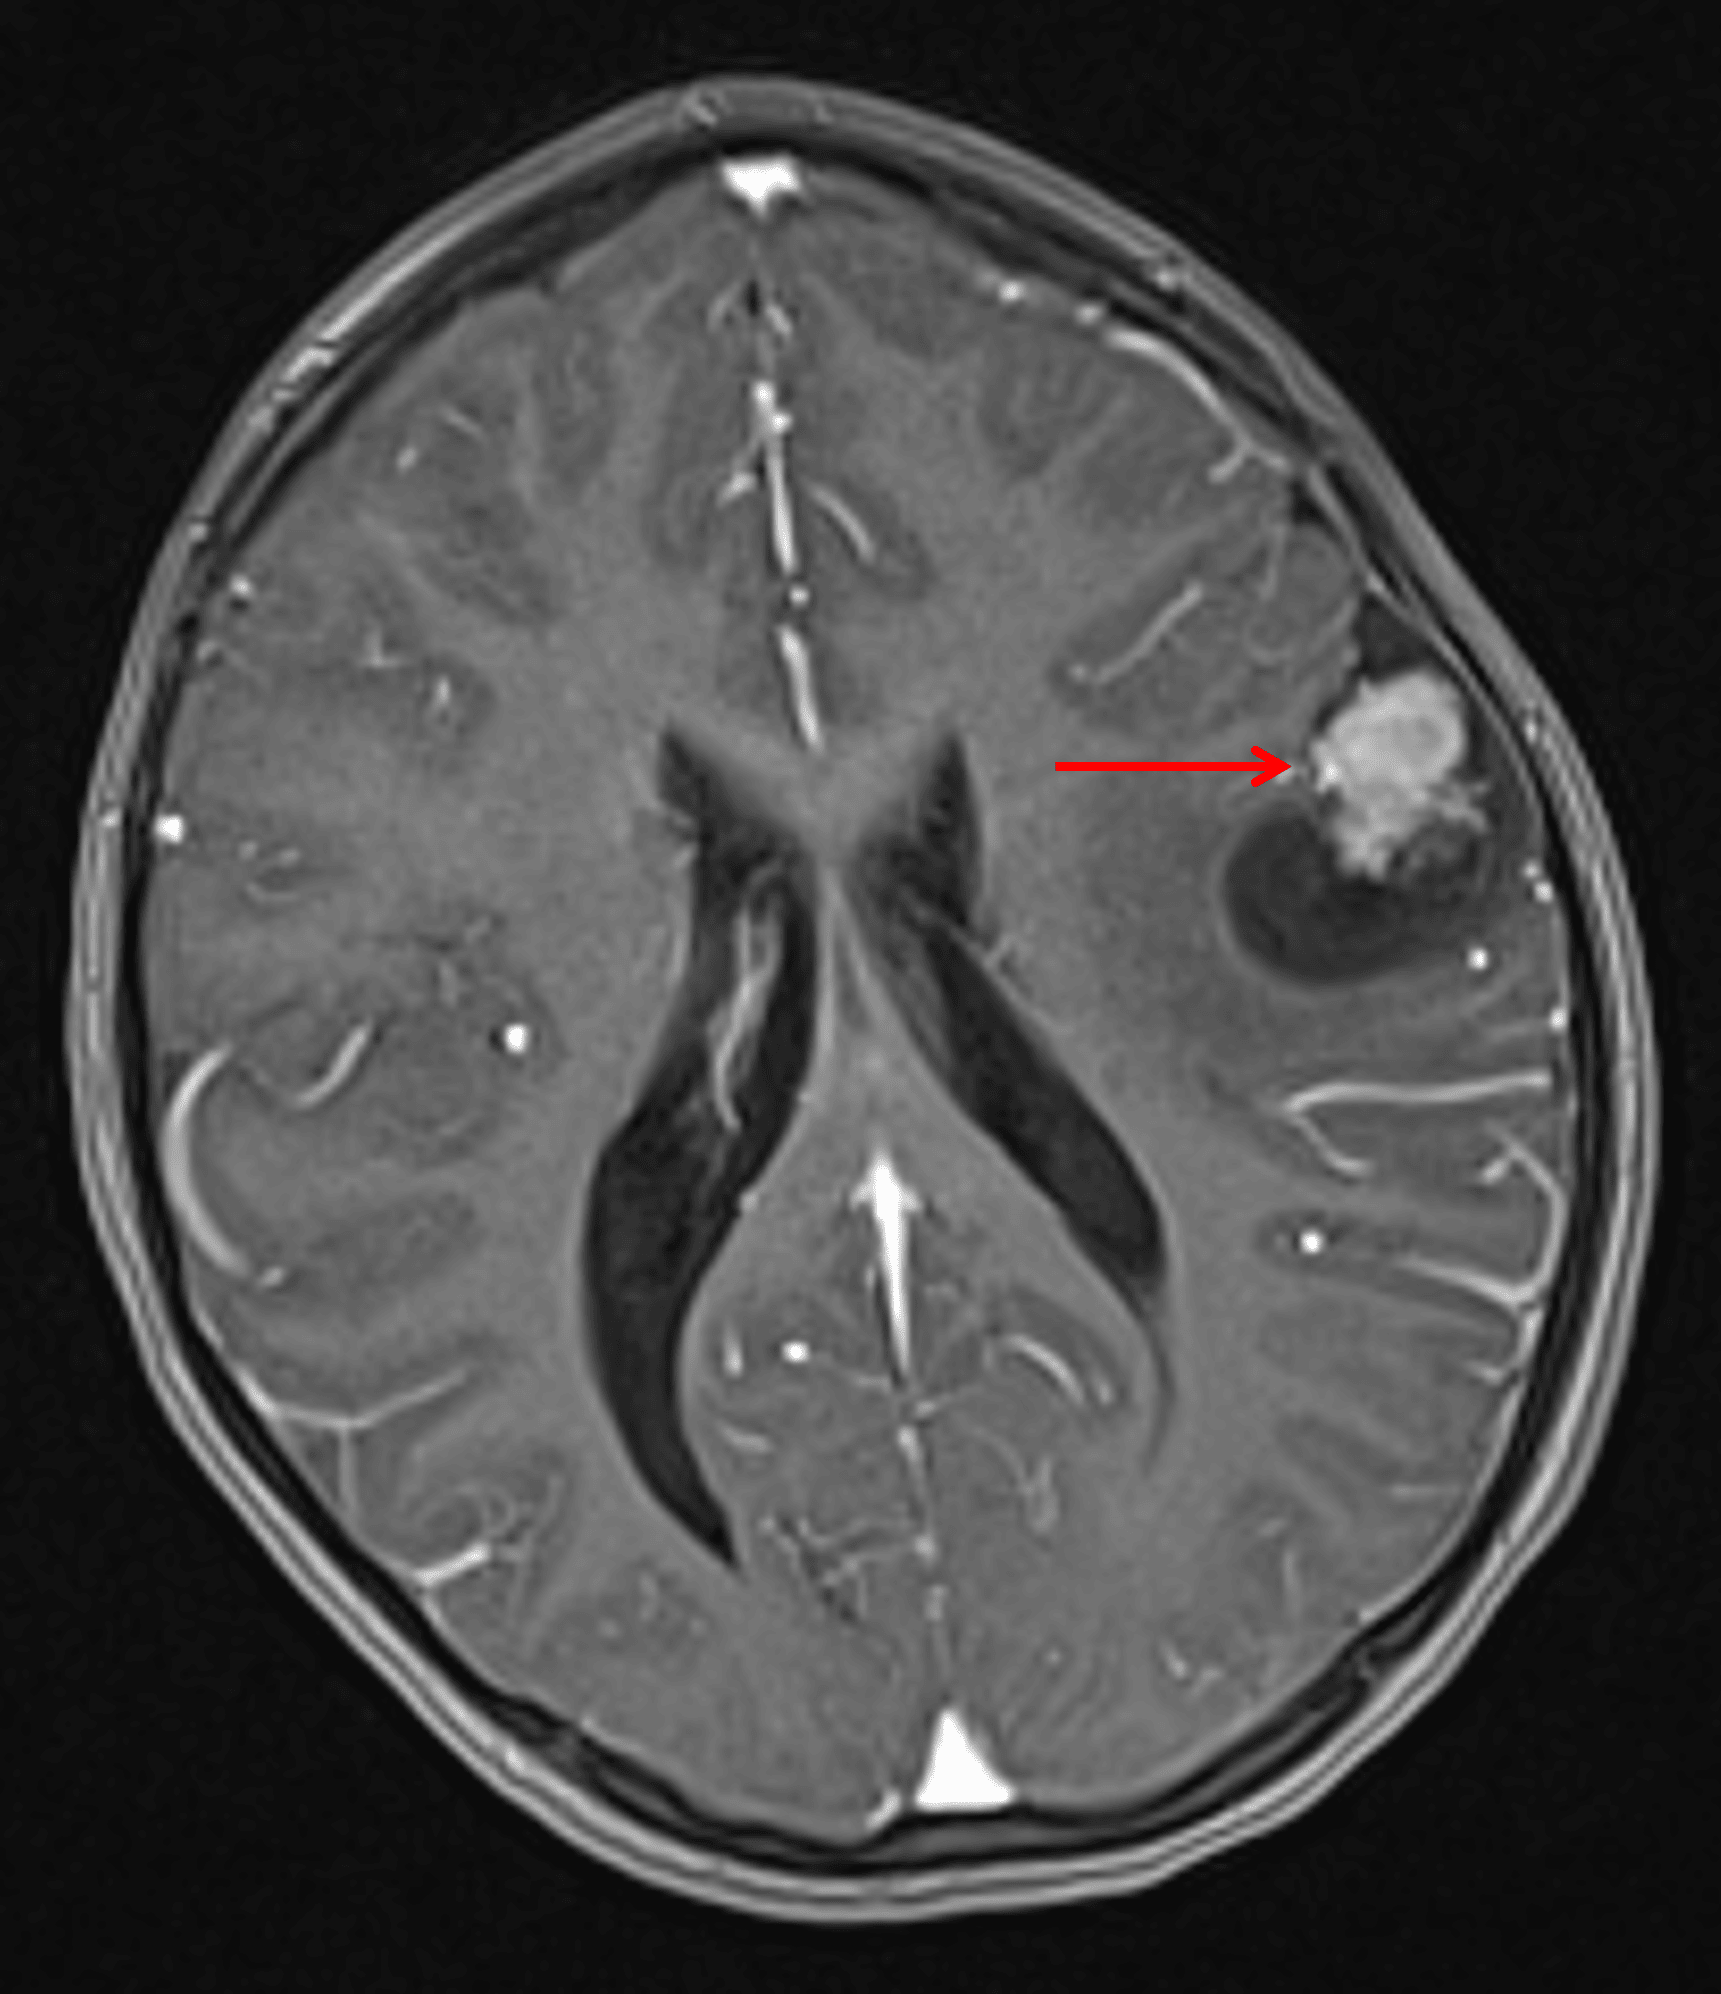

Findings

- Cortically-based, mixed cystic and solid mass centered in the left inferior frontal gyrus

- The solid component avidly enhances

- Focal subarachnoid space enlargement overlying the mass

- Mild surrounding vasogenic edema and local mass effect without midline shift

Annotated Images & Illustrations

Mixed cystic and solid tumor in the inferior left frontal lobe (red arrow).